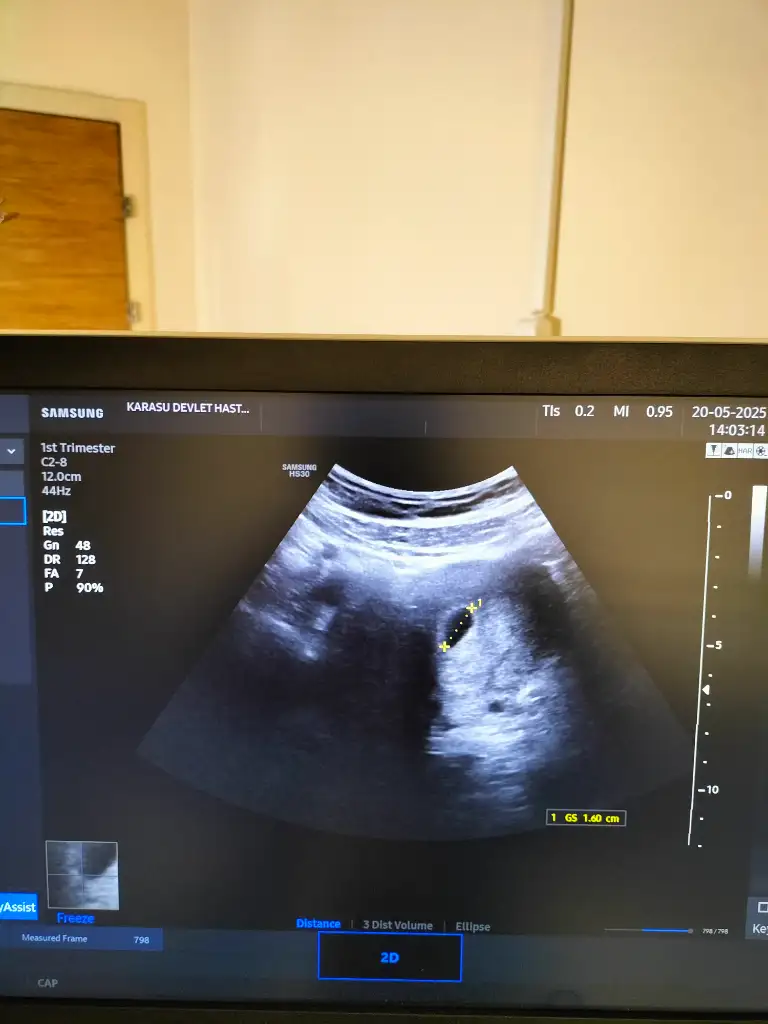

Ya bende 26sı özele gidicem ben şey duydum özeldeki aletler ile devlettekiler aynı kalitede değilmiş ondan görünmüyormuş misal ben 5+5 iken devlete gittim keseyi hiç göremedi o kadar bastırdı ki aşırı rahatsız oldum, ertesi gün 5+6 iken özele gittim ultrasonda bastırmadı bile direkt gözüktü çok şaşırdım ama bence cihazla ilgili, haberleşelim yine 26sı gidersenCanım ben dün tesadüfen boş bir randevu bulmuştum başka bir doktora, bu sabah gittim sadece kese gorunuyor dedi kalp atışı icin 2 hafta sonra gel dedi, ben normalde biliyosun 26 veya 27si gidicektim bu seferde beni 3 hazirana attısinirden gülüyorum… yani 2 hafta sonra 2 aylık olcak nerdeyse ya… hadi bir hafta ertelersin de 2 hafta nedir. Zaten hiç ilgili bir doktor değildi oturmam ile kalkmam 30 saniye sürmüştür. Ama ben kararımı verdim 26sı varya o gün özele gidicem. O zaman 7 haftalık oluyorum şansımı denicem. sende 26sı gidiyordun değilmi ümraniye demiştin sanki

Hayırlısı inşallah az kaldıııYa bende 26sı özele gidicem ben şey duydum özeldeki aletler ile devlettekiler aynı kalitede değilmiş ondan görünmüyormuş misal ben 5+5 iken devlete gittim keseyi hiç göremedi o kadar bastırdı ki aşırı rahatsız oldum, ertesi gün 5+6 iken özele gittim ultrasonda bastırmadı bile direkt gözüktü çok şaşırdım ama bence cihazla ilgili, haberleşelim yine 26sı gidersenhakkımızda hayırlısı olsun zaten 26sını bekleyemiyoruz bi de haziran hiç beklenecek gibi değil evet ümraniyeydi ama özeldeki de 26sına randevu vermişti o yüzden devleti son ana kadar iptal için bekliyordum

Ayrıca sana 5+3 olduğunu Dr mu söyledi. Kese 10mm iken 4+6 falan olması gerekiyor diye biliyorum .çünkü ben ilk kontrole gittiğimde sat a göre 6+5 dim.ultrasonda 4+5 olduğumu ve 9mm kese olduğunu ve ortalama günde 1mm büyür kese ve Max 20mm de bebek gorunur dedi doktorum.velhasil geç döllenme olmuş benimki seninkide öyle olabilir geriden geliyor olabilir yani.doktor sat a göre değil ultrasona göre ilerleyecek haftan dediİnşallah kızlar çok sağolunaslında bu kadar şey bilmesem daha rahat geçecek zaman. Bu haftada yolk sac gözükürü öğrendiğimden beri böyleyim. Cahillik en büyük mutluluk gerçekten ya